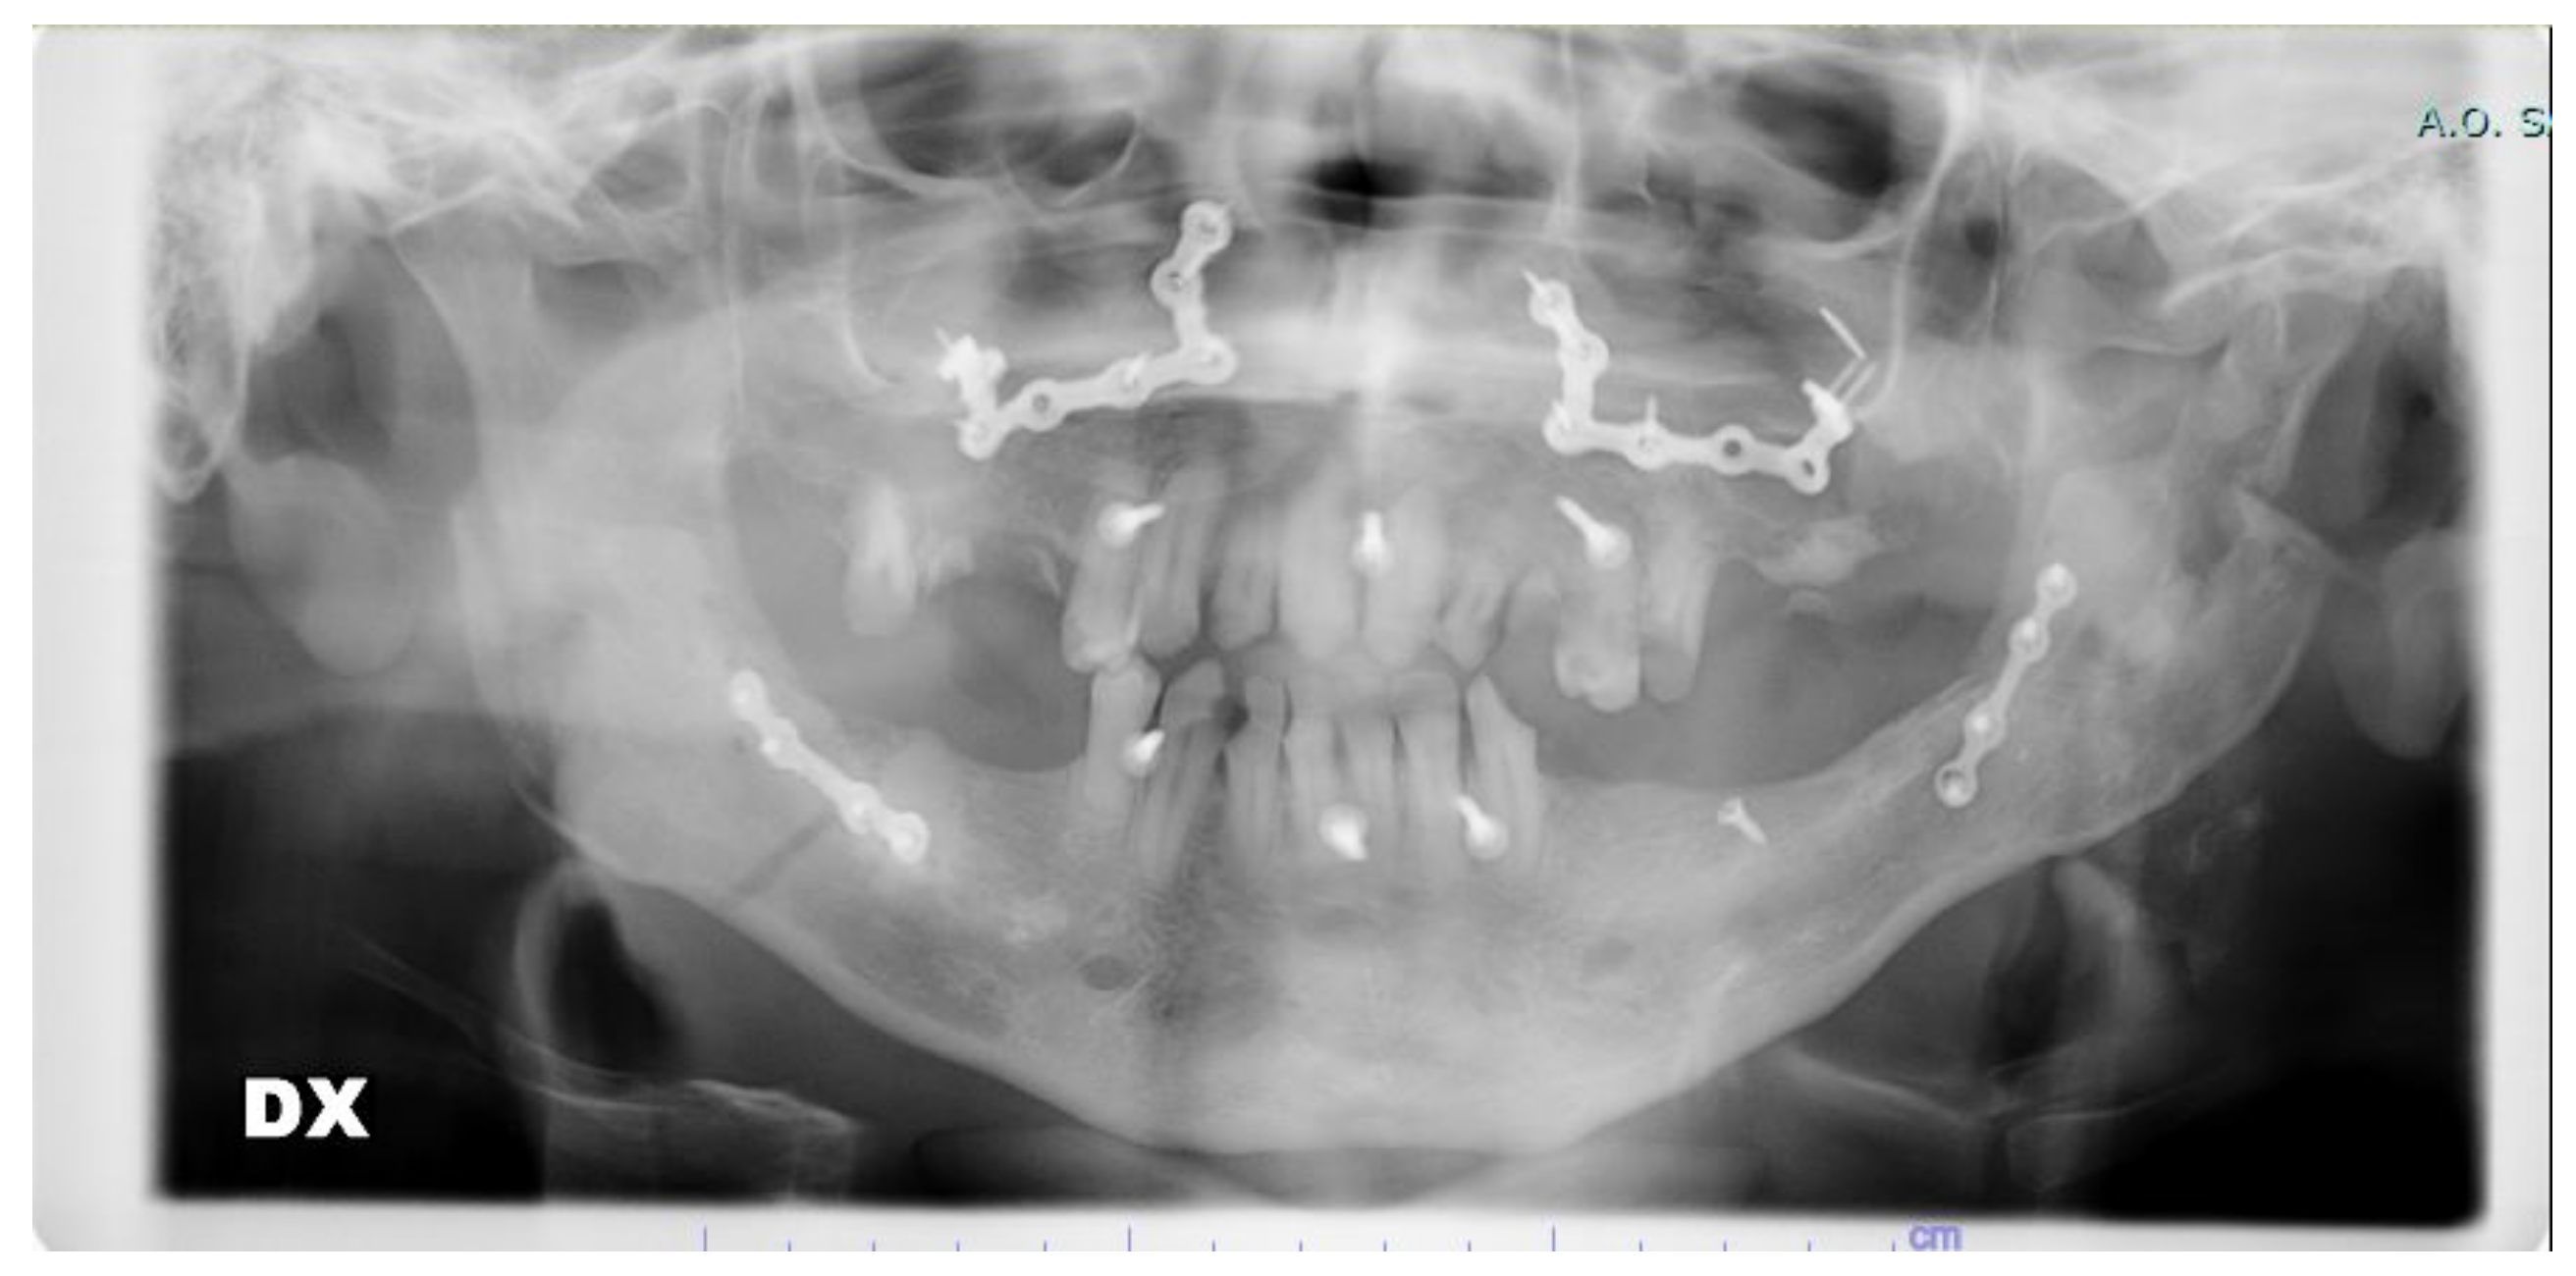

The procedure was adopted in one clinical case on a patient affected by a class III malocclusion with an associated open bite and right deviation of the mandible. The patient was a 27-year-old male already operated on 5 years prior for multiple fractures of the jaw after a car accident. Screws and plates from the previous operation were removed before new orthognathic surgery. Following our procedure, a high-definition skull CT scan was acquired and digital planning was performed. Evaluation of proper maxillary and mandibular segmentation and movements was performed considering class III, open bite, and asymmetry correction. Additionally, evaluation of gap or overlapping of the bone fragments at the osteotomy sites was acquired up to a final bone fragments positioning feasible in relation to anatomic and surgical technique limits. CAD/AM (Computer-Aided Design/Computer-Aided Manufacturing) surgical guides and custom-made fixation plates were acquired before surgery. In this special case, the standard plates were unable to be used for the particular conformation of the bones.

The surgery to which the patient was subjected required a BSSO and a Le Fort I osteotomy.

In the following figures, the medical images, orthopanoramic images (Figure 6 and Figure 7) before and after an orthognathic surgery, the implanting screws (Figure 8), and a digital reconstruction (Figure 9) are shown.

Operation was conducted without particular difficulties with the aid of the surgical guides and custom-made plates and screws fixation system. Surgical guides precisely fitted in the planned facial skeleton areas and pre-drilling holes precisely combined with custom-made plates holes resulting in proper jaw positioning and dental class I occlusion. Additionally, the amount of bone gap and overlapping at the osteotomy sites was restrained to an acceptable degree in relation to anatomic and surgical limits by proper planning combining main skeletal advancement for the upper jaw (5 mm) with a limited amount for mandibular set-back (3 mm) combined with left rotation of the lower midline up to precise fitting with the upper midline.

Figure 9. Digital reconstruction.